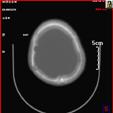

3).颅骨凹陷性骨折术前 术后

4).颅骨修补术 DR片 三维重建